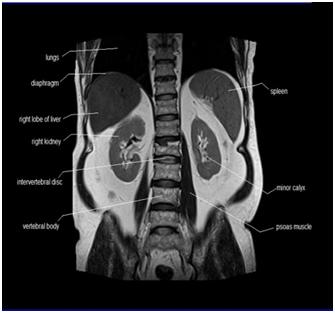

MRI of the Abdomen

Your doctor has ordered a MRI (Magnetic Resonance Imaging) of your abdomen. MRI uses a magnetic field, radio waves, and a computer to create images soft tissues, bones, and internal body structures. MRI of the abdomen allows physicians to examine the abdominal anatomy to rule out any structural abnormalities.